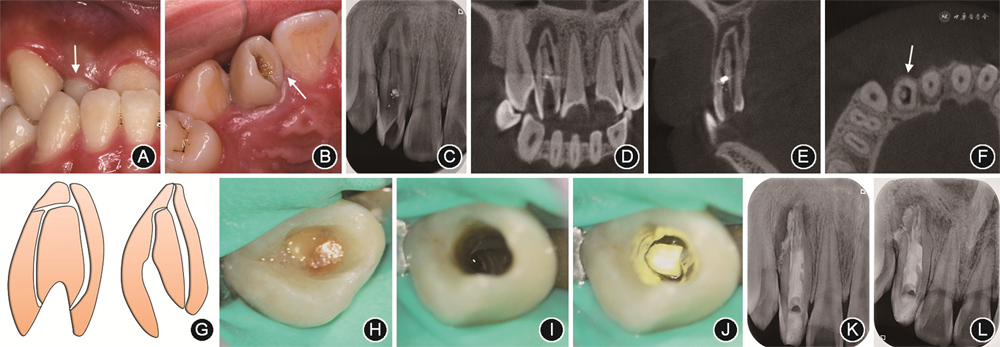

患者女性,31岁。2018年12月因“右上前牙牙龈脓包,吮吸有咸臭味2个月”就诊。无冷热痛、自发痛或咬物痛。患者既往体健,否认全身系统性疾病史及传染病史,无药物过敏史,无牙外伤史。

(1)临床检查:面型对称,张口度正常,关节无弹响,张口无偏斜。口内检查:12牙冠过大,唇侧根尖区见一米粒大小脓包,腭侧釉质内陷(图2A,B)。垂直叩痛(+),水平叩痛(-),不松动,牙周探诊无附着丧失,冷热测试及电活力测试均无反应。全口游离龈及龈乳头呈暗红色,牙龈组织肿胀,龈缘变厚,龈乳头圆钝松软,牙龈点彩消失,表面光亮,全口出血指数为3,龈沟内渗出液增多。

(2)影像学检查:根尖片示12牙冠部硬组织内陷腔低密度影,多根管影,根尖孔呈喇叭口状,根尖周低密度影(图2C)。锥形束CT示12牙冠内陷从釉质至根尖1/3,两个主根管影像清晰,中央有一内陷小牙,牙周膜增宽,根尖部可见假性根尖孔,根尖区见6.0 mm×7.2 mm×5.5 mm大小的根尖区低密度影像,边界清晰(图2D~F)。

(3)诊断:12慢性根尖周炎;12牙内陷(Oehlers Ⅲb型)(图2G);慢性牙龈炎。

第1次治疗:见图2H。橡皮障隔离患牙,显微镜下开髓,探查根管口,探及2个主根管(近中和远中)及内陷腔。使用10号K锉疏通根管,确定工作长度:近中根管17 mm,远中根管18 mm,机用镍钛锉Mtwo(VDW,德国)预备至35号0.04锥度,化学预备方法同病例1。

第2次治疗(首次治疗10 d后):见图2H。根管清理,根管激光荡洗与消毒方法同病例1。纸尖干燥根管后用垂直加压器行三氧化矿物凝聚体(mineral trioxide aggregate,MTA)(ProRoot MTA,登士柏,美国)根管充填,每2 mm使用超声加压,显微镜下观察根管口充填情况,拍术后根尖片(图2I)。髓腔内封湿棉球1周,探查MTA完全固化后,使用加强型流动树脂(Beaufil Flow Plus F00,松风公司,日本)充填髓腔,抛光。术后3、8、30个月复查,根尖片显示根尖阴影逐渐缩小,术后30个月时根尖周病变基本愈合(图2J~L)。